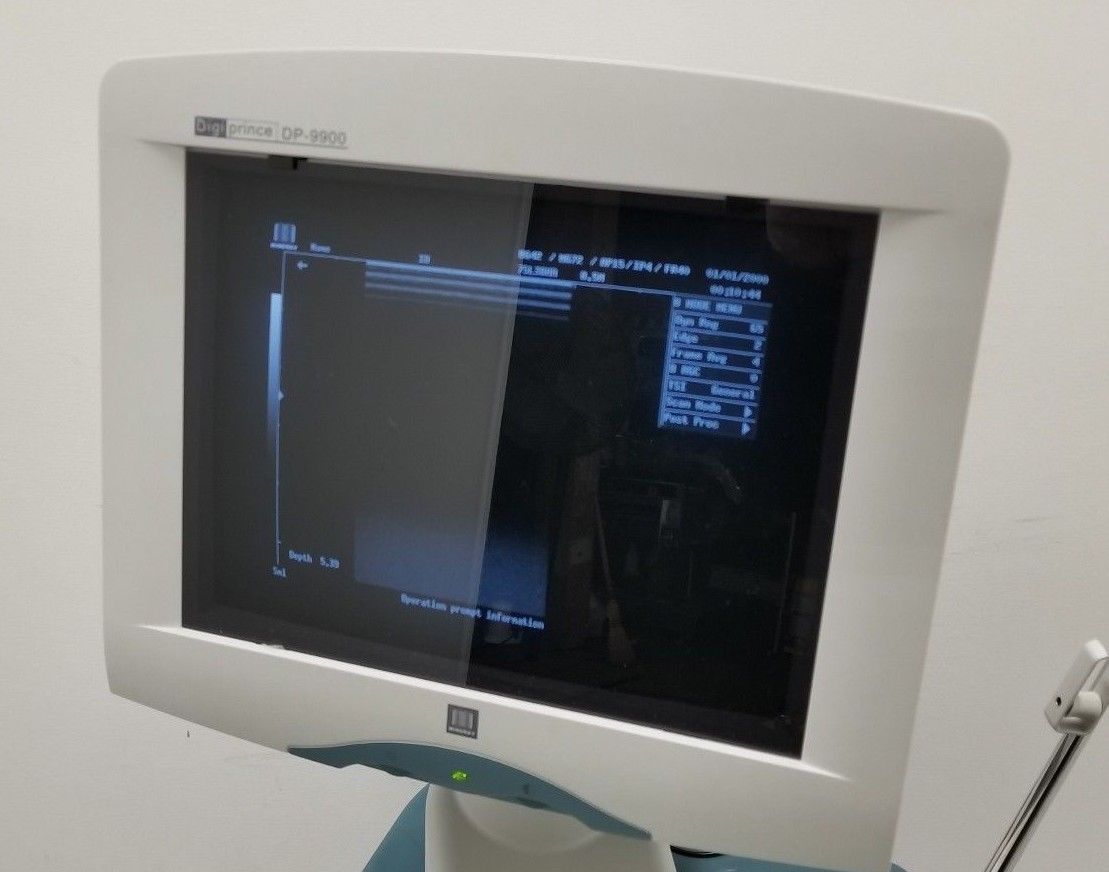

DIAGNOSTIC ULTRASOUND MACHINES FOR SALE

Mindray DigiPrince DP-6600 Ultrasound Machine with Transducer

Sale price$ 10,492.00

Regular price$ 11,192.00

Save $ 350.00